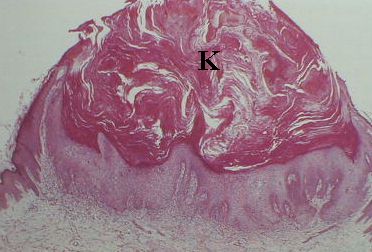

Low magnification H&E

The specimens show presence of epidermal hyperplasia with

central crater containing keratin (K). The lesion is well demarcated

from the surrounding (adjacent and deeper) tissues.